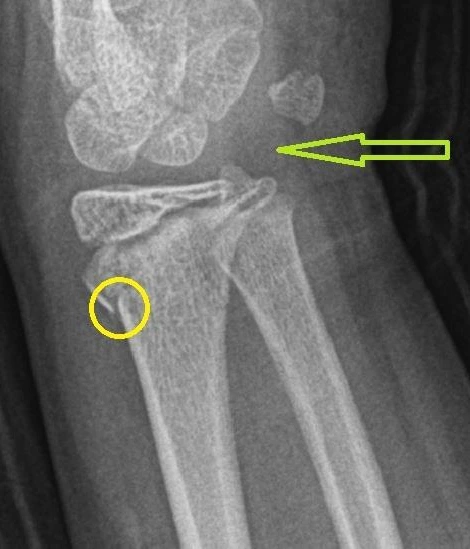

엑스레이 검사, 소위 말하는 단순 방사선 검사는 X-선을 우리 몸에 투과시켜서 이미지를 얻는 검사이다. 이러한 단순 방사선 검사를 통해서 노출되는 방사선 선량은 생각보다 많지 않음으로 검사 자체의 방사선 선량에 대해서는 크게 걱정하지 않아도 된다. (방사선 선량에 대한 좀 더 자세한 정보는 지난 글 https://brunch.co.kr/@hansoltop/59 참고 부탁드린다.) 다만 3차원 구조를 방사선이 통과한 후, 한 방향(2차원 평면)으로 영상을 만들기 때문에 구조들이 중복되고 겹쳐 보인다. 또한, 뼈를 제외한 나머지 구조의 경우 방사선 영상에서 다 비슷비슷한 정도의 음영으로 나타나기 때문에 실제로 병변이 있는지 없는지 구별하기가 쉽지 않다. 기본적으로 엑스레이 검사는 뼈를 보는 검사라고 생각하면 편하다. 아래 사진을 보면, 노란 원안의 골절은 의학적 지식이 없이도 눈에 들어오지만 초록색 화살표가 가리키고 있는 부위에는 인대, 힘줄, 관절 등이 복합적으로 있지만, 알고 봐도 하나하나 구조를 가려내기란 거의 불가능하다.

ped radius fracture.JPG